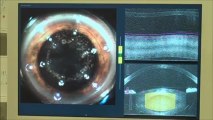

Cataract surgery is the only way to correct cataracts. The procedure involves the removal of the clouded lens and replacing it with an artificial intraocular lens. It is a simple and safe procedure with a very high success rate. The procedure itself usually lasts only 5 to 8 minutes. How well you see after surgery will vary. Outcomes can depend on lens selection, OR technology, and the surgeon’s experience.

Here at the Eye Institute of West Florida we specialize in providing cataract patients custom lens options that are designed to help them see clearly at all ranges of distance without the aid of glasses and contacts all the time. Because every eye is uniquely different, we offer a multitude of specialty lenses that meet the custom need of each individual patient. Our operating rooms are equipped with the world’s finest vision systems. It is quite possible we are the only facility with not one, but two femtosecond cataract laser units and among very few ambulatory surgery centers in the United States with a real-time refraction system.